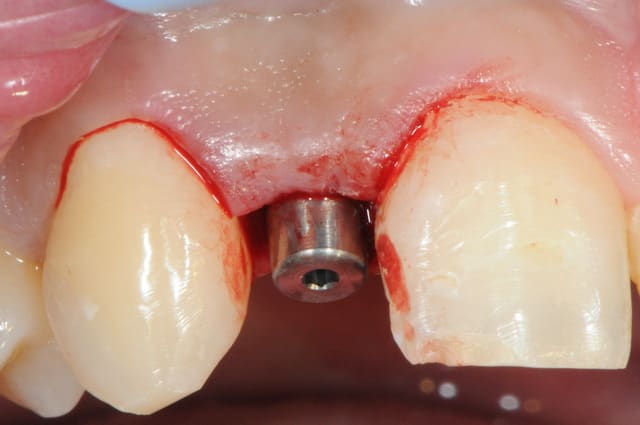

-cicatrisation de la première vis de cica,

-diamètre plus gros pour la vis de cica

- pilier pour la provisoire

- provisoire moule ION

- ajustage

- polissage soigneux

la suite tout à l'heure, ça sonne à la porte...